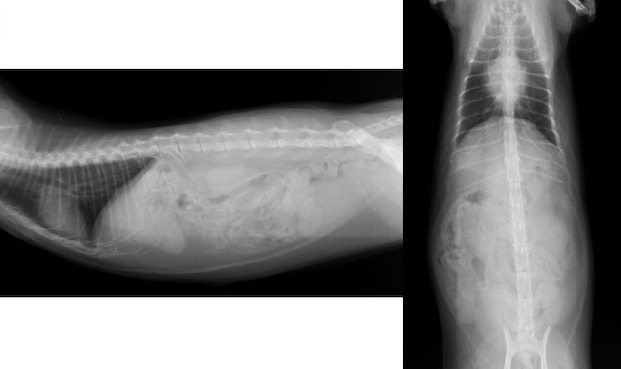

当院での画像検査所見です。

レントゲン検査画像です。